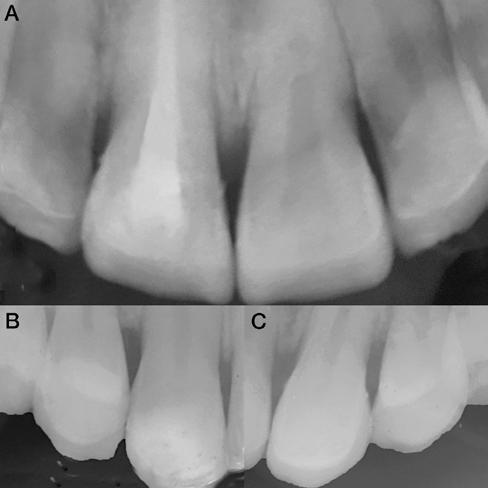

2. ábra: Az okkluzális nézet a fogszerkezet mennyiségét mutatja, a röntgenfelvételen az 1.5. fogon II. osztályú szuvasodás is látható. Még ha lehetséges is ezeket az eseteket koronahosszabbítással kezelni, a végeredmény átlagosan nem kielégítő. A ferrule gyógyulása korlátozott, és olyan parodontális szövődményekkel is találkozunk, mint a fekete háromszögek, a szomszédos fogak gyökérkitettsége. A fogszabályozó extrúzió sokkal előnyösebb.

10. ábra. A négyéves kontroll alkalmával készült röntgenfelvételek. (A): A metszőfogakról készült koronafelvétel. (B): A jobb oldali szemfog és első kisőrlőfogról készült koronafelvétel. (C): A bal oldali szemfog és első kisőrlőfogról készült koronafelvétel.